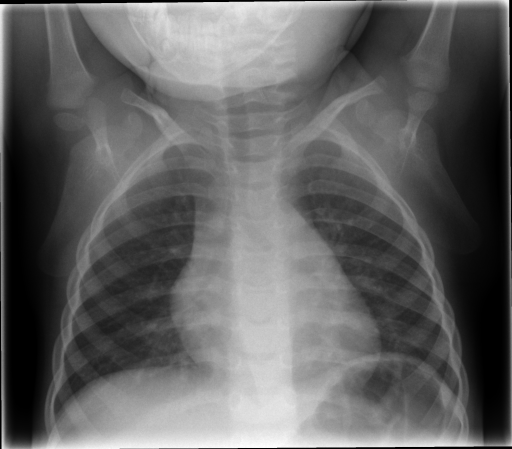

Figure 3 shows some samples images from IRMA dates along with their corresponding IRMA codes.